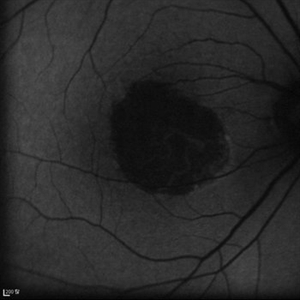

Geographic atrophy

Aug 29 2012 by Young Hee Yoon, MD, PhD

FAF image of an 78-year-old woman. Her best-corrected visual acuity was counting fingers at 30cm.

Photographer: Kyoung Woon Kim, Asan Medical Center

Imaging device: Heidelberg

Condition/keywords: dry age-related macular degeneration (dry AMD), geographic atrophy